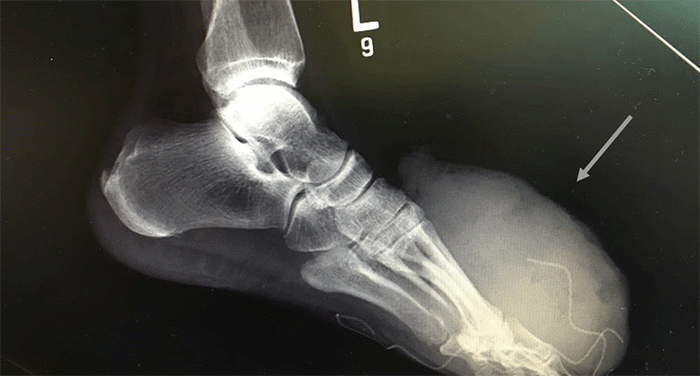

A 56-year-old male with a medical history of undiagnosed hypertension and hyperlipidemia presented to the emergency department via EMS with a left mid-foot exophytic hemorrhagic mass. Examination revealed a large (approximately 20 × 15 cm) necrotic and hemorrhagic tumor on the plantar aspect of the left foot. The mass exhibited friability and significant vascularity (Figure 1).

Figure 1. Preoperative Left Foot Radiograph Demonstrates Synovial Sarcoma (approximately 20 × 15 cm). Published with Permission